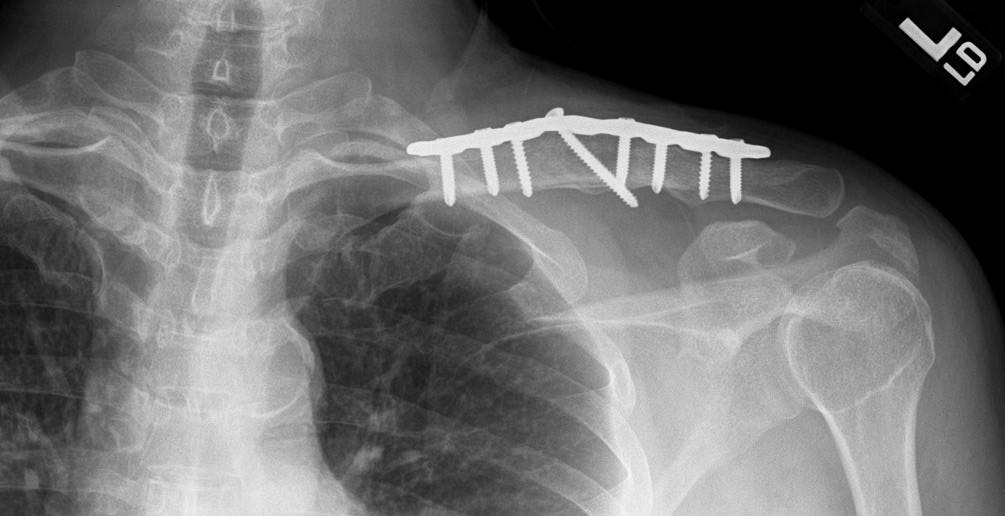

This patient’s nonunion was treated by removing the existing plate and implanting a new plate with bone graft to stimulate healing. This x-ray taken 8 months later shows solid healing of the clavicle. The patient had no pain and full motion in his shoulder.